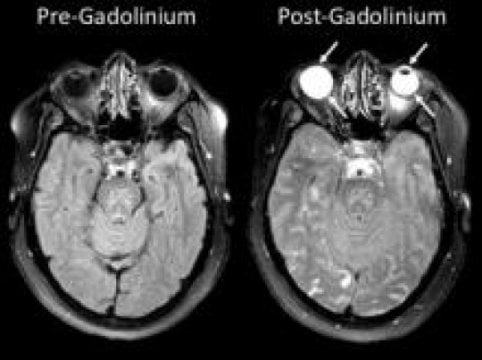

Eye could provide “window to the brain” after stroke

Preliminary results suggest strokes also affect the eye.

Research into curious bright spots in the eyes on stroke patients’ brain images could one day alter the way these individuals are assessed and treated. A team of scientists […]